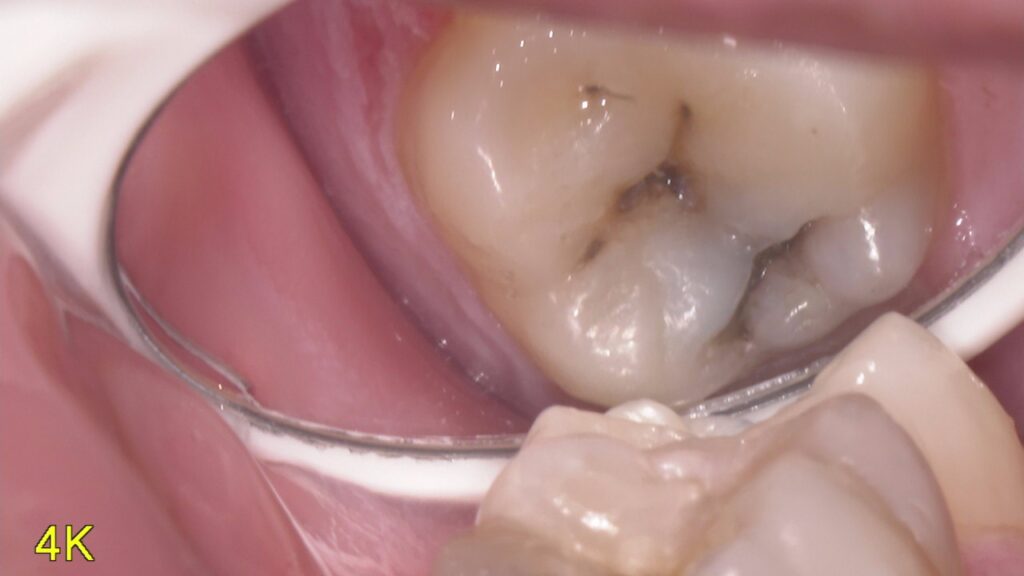

虫歯って患者さん本人には見えない位置にあったりしてなかなわかりにくいですよね

そのために当院では口腔内カメラを内蔵したマイクロスコープを使用して口腔内を説明しています。

写真を撮ったり、動画を撮ったりいろいろ使えるので重宝しています。

今回の写真は普段見えない位置の虫歯を撮影してみました。まだ小さいので症状はなにもないですが放置していたら広がってかけたり痛みが出てくると考えられるのでその前にしっかりと治していくのが大事です。

どんだけお話しするより現物を見てもらったほうがイメージわきますしどうなってるかわかるのでやはり動画や写真は大事なんだなと痛感しています。